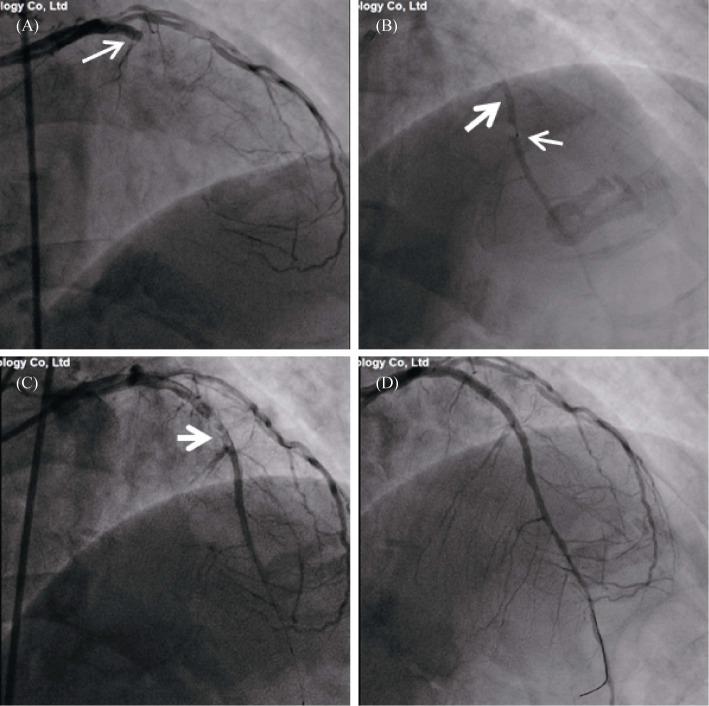

METHODS & RESULTS: Eight patients underwent ICART. The guidewire was advanced to the distal coronary artery through the occlusion lesion. Then, we inserted a microcatheter into the distal end of the occluded coronary artery over the guidewire. Urokinase (5-10 wu) mixed with contrast agents was slowly injected into the occluded section of the coronary artery through the microcatheter. The intracoronary thrombus gradually dissolved in 3-17 min, and the effect of thrombolysis was visible in real time. Stents were then implanted according to the characteristics of the recanalized culprit lesion to achieve full revascularization. One patient experienced premature ventricular contraction during vascular revascularization, and no malignant arrhythmias were seen in any patient. No reflow or slow flow was not observed post PCI. Thrombolysis in myocardial infarction flow grade and myocardial blush grade post-primary PCI was 3 in all eight patients. No patients experienced bleeding or stroke.

ICART was accurate and effective for treating intracoronary thrombi in patients with STEMI in this preliminary study. ICART was an effective, feasible, and simple approach to the management of STEMI, and no intraprocedural complications occurred in any of the patients. ICART may be a breakthrough in the treatment of acute STEMI.